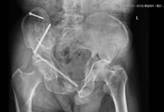

3)复杂四肢骨折与关节损伤、复杂骨盆髋臼骨折的治疗:精于四肢复杂骨折与关节损伤的闭合手法复位及微创固定,骨盆骨折的微创治疗、复杂髋臼骨折、下肢多发骨折闭合复位内固定、小儿骨折手法闭合整复复位穿针内固定。

4)髋膝关节置换:擅长各种复杂髋膝关节的置换。

置换前 | 置换后 |